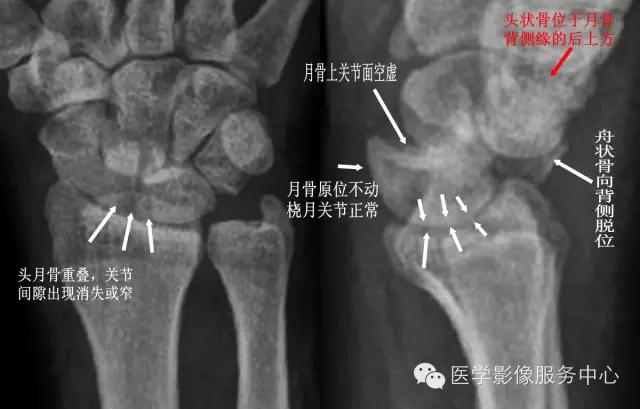

三、月骨周围脱位 【受伤机制】 摔倒时手背伸、尺偏和旋前位着地,发生月骨周围脱位。【临床表现】 腕部肿胀向背侧突出,屈伸活动受限,局部疼痛、压痛。 【诊断要点】

①正位片上头月骨重叠,关节间隙出现消失或变窄;

②侧位片上月骨原位不动,桡月关节正常,月骨上关节面空虚;

③头状骨位于月骨背侧缘的后上方;

④舟状骨向背侧脱位;

⑤可伴有桡骨背缘骨折。